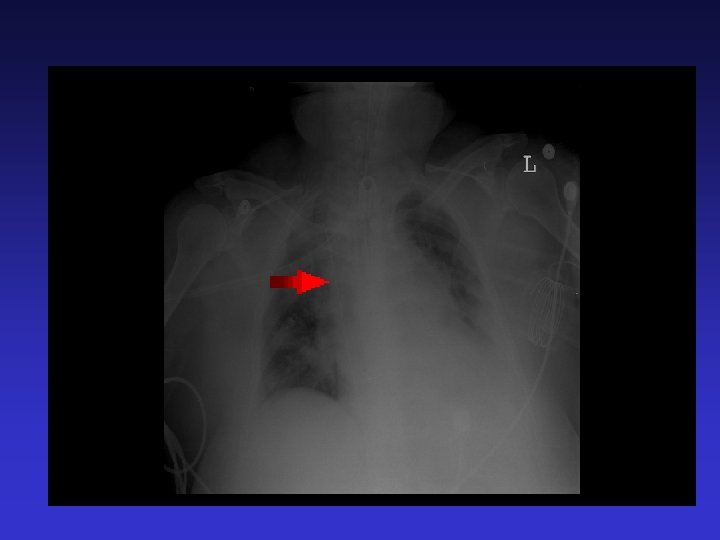

Central Venous Catheter Insertion